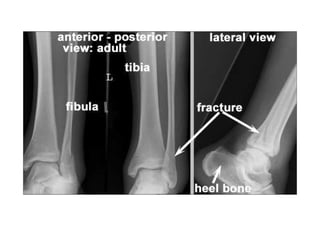

RADIOLOGIA DO

TRAUMA DO ESQUELETO

Referência: http://www.accessexcellence.org/RC/VL/